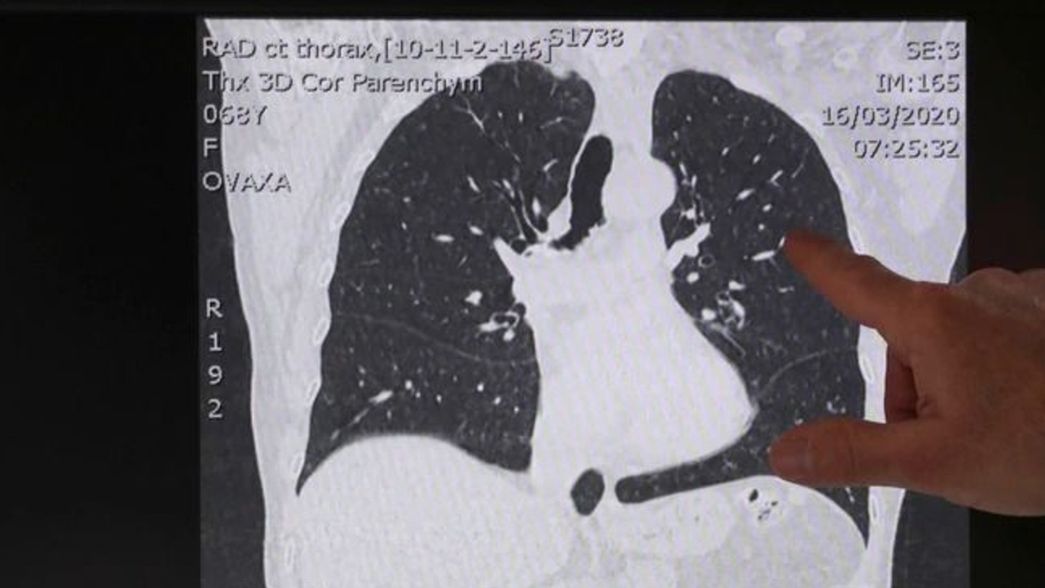

Cuáles son los cuatros tipos de pacientes con coronavirus y qué le pasa a los pulmones